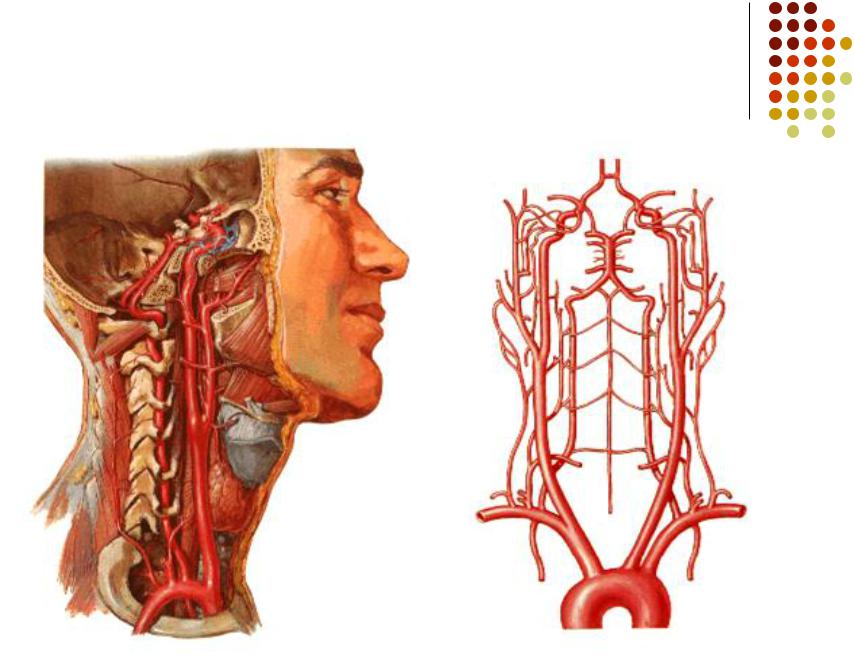

Особенности и диагностика левостороннего кровотока